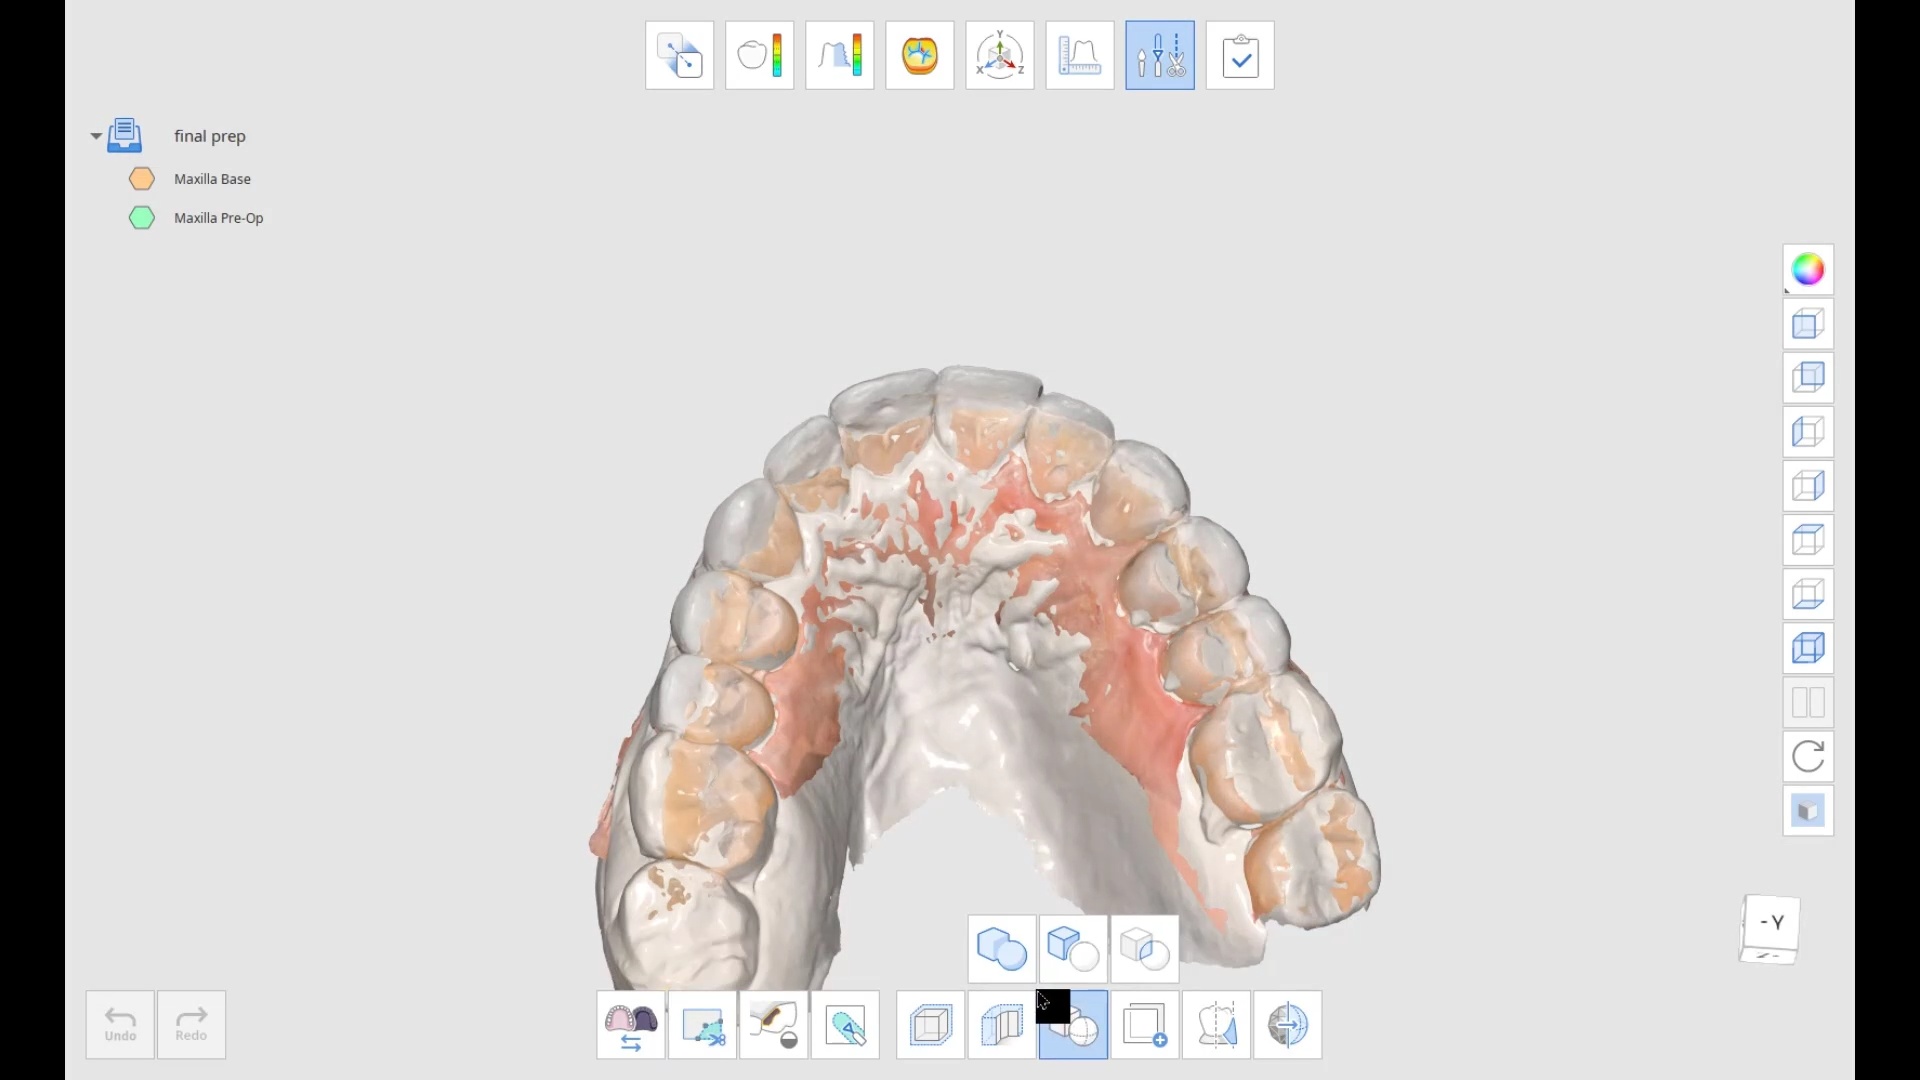

March 17, 2022the patient was sedated and intubated for the case so we could not keep track of the bite. Instead, we imaged all 30 prepared teeth and used medit compare […]

the patient was sedated and intubated for the case so we could not keep track of the bite. Instead, we imaged all 30 prepared teeth and used medit compare […]

Medit Compare, now called Medit Design, now has a boolean cut feature that lets you extract a temporary shell model from wax up or mock up model and prep model […]